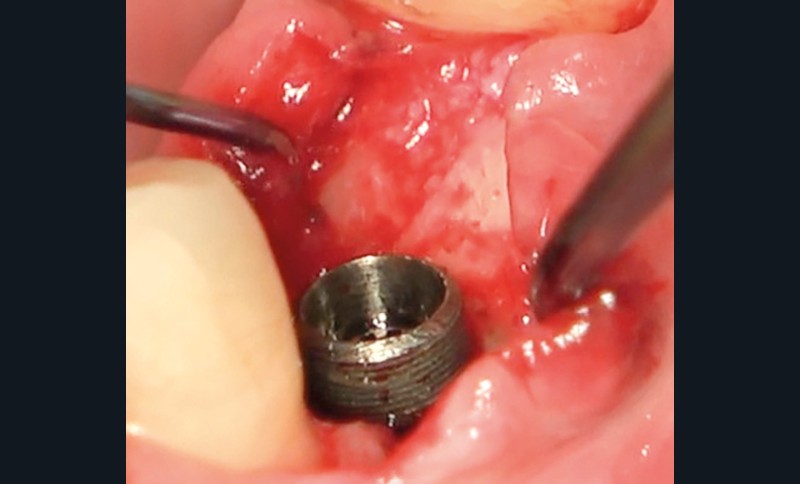

- Péri-implantite diagnostiquée en 2021

Chez ce patient, le traitement de la péri-implantite a comporté une chirurgie associant décontamination électrolytique de la surface implantaire, régénération osseuse guidée et enfouissement de l’implant. Le résultat à 2 ans est très moyen au vu du pourcentage de régénération osseuse obtenu. Comment peut-on prévoir un tel résultat alors que l’on a suivi les recommandations à la lettre, que l’on a utilisé les dernières technologies de décontamination, que l’on y a mis tous les moyens, que le patient est en bonne santé générale et qu’il vient en plus régulièrement aux séances de thérapeutique de soutien ? Le succès du traitement des péri-implantites n’est pas simple à obtenir, surtout quand un élément clé est compromis… la maintenance personnelle ! En effet le succès n’est possible que si le contrôle de plaque quotidien est optimal et, ici, ça n’était pas le cas. Le patient se brossait certes les dents, mais ne passait pas quotidiennement les brossettes, ce qui…